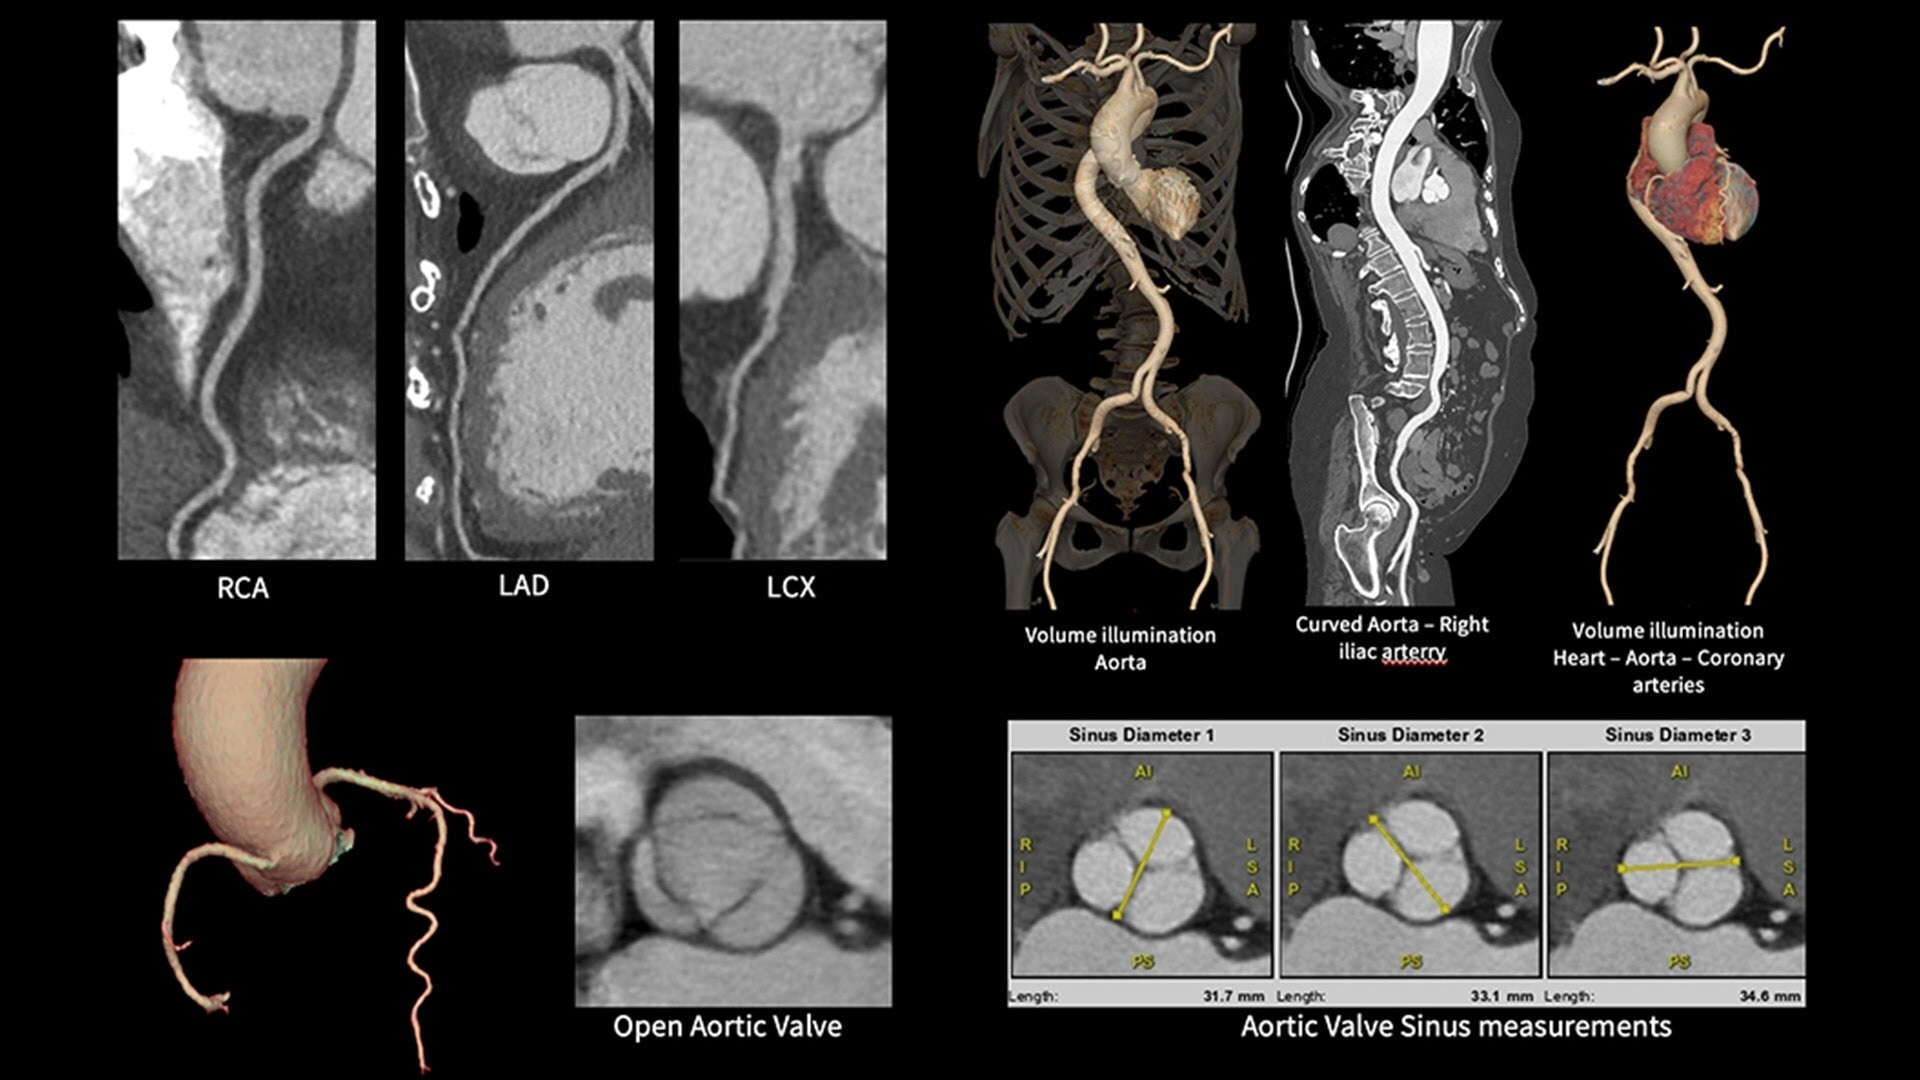

The ECG-less CT (a cardiac CT scan without an ECG trace) is an industry-first

Increases Cardiac CT access

Address cardiac exams where patient access and speed need to be prioritized

Simplified workflow

Useful in exams where excluding ECG traces would streamline patient preparation